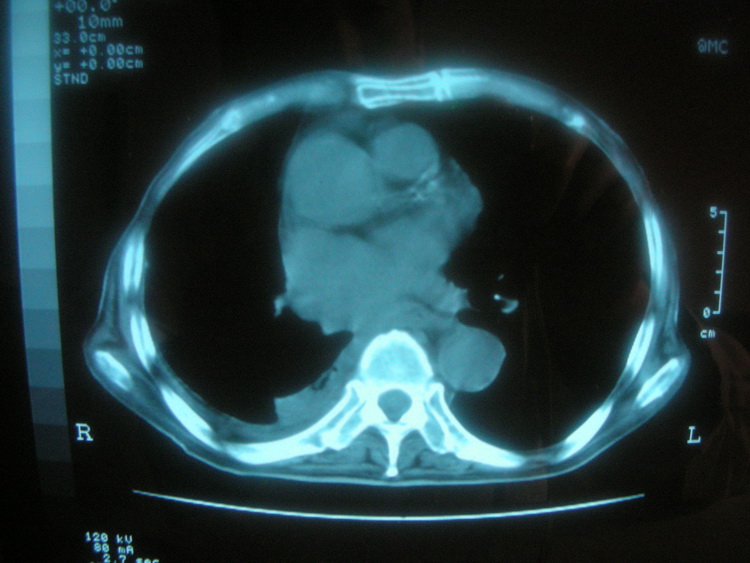

以下是引用卜一在2008-2-16 6:10:00的发言:[br]右肾增大,实质内明显见占位性病灶,并突出体外,密度不均匀。另双肺上叶见散在的斑片 索条及点状结节样致密影,右下肺门区不规则团块,右侧胸腔积液并形成局限性气胸。考虑:1 右肾癌。2 右肺门淋巴结转移及肺内 胸膜转移。3 右上肺陈旧结核。

以下是引用zjzjr在2008-2-16 14:15:00的发言:[br]1 右肾癌伴 右肺门淋巴结转移及肺内 胸膜转移。2右侧胸腔积液引流后改变(可见引流管影)3 双上肺继发型结核。